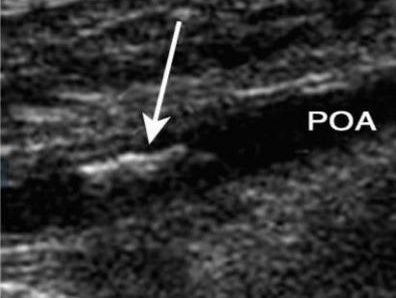

动脉硬化性闭塞症是在动脉硬化基础上发展成的以动脉狭窄或闭塞性改变为特征的疾病,是一种全身性疾病,主要累及大动脉和中动脉,最常见于下肢动脉。

早期症状为病肢冷感、苍白,进而出现间歇性跛行。后期病肢皮温明显降低、色泽苍白或发绀,出现静息痛,肢体远端缺血性坏疽或溃疡。

动脉硬化性闭塞症患者早期常无明显症状,容易漏诊,特别是长期吸烟及高血压患者应重视体检时行下肢血管彩超检查。